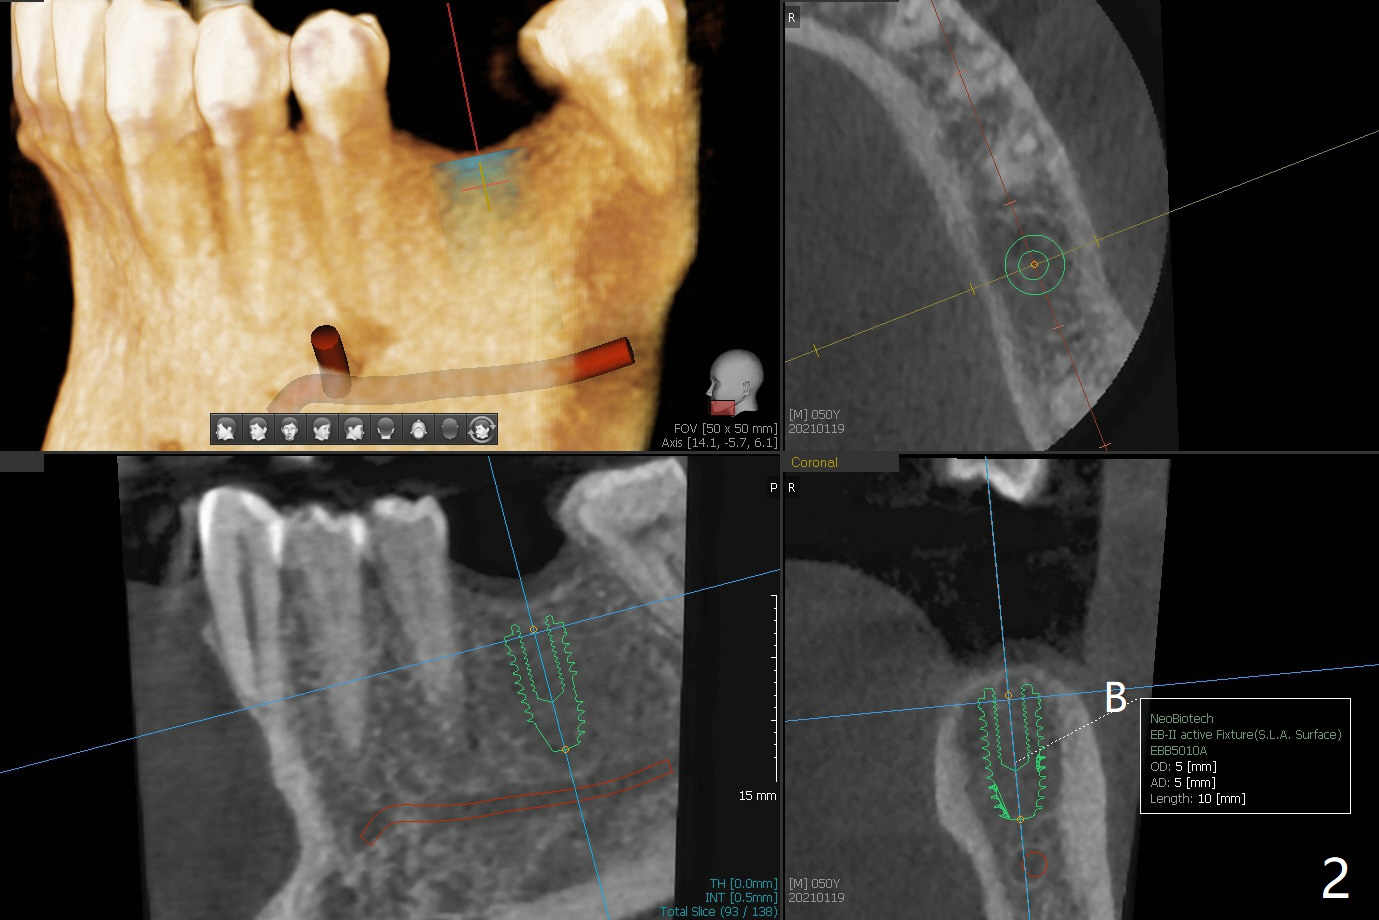

50岁男缺失3个磨牙(包括左下6,图一),左下7严重磨损,树脂修复三次(*),终于同意先做左下种植(图二),骨质宽,但是密度低,可能需要小号钻头,愈合时间多些